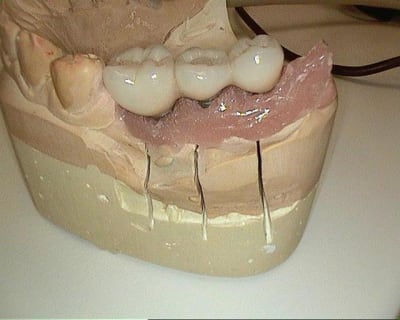

une fin cas en passant. 7 semaines après implantation.Je n'ai pas les photos du début du cas ici mais si cela intéresse quelques uns je peux les mettre en rentrant.

je poste tout de même la suite ( ou plutôt le début ) du cas.

le dernière photo c'est 8 semaines après les autres le jour de l'implantation.

des photos d'un cas d'aujourd'hui avec le shuttle retiré ( 8 premières photos)

les 4 dernières c'est avec le foret , la dernière photo c'est un cas d'extraction implantation d'aujourd'hui aussi on voit la nouvelle alvéole après le forage ( désolé pour la qualité de photo...)